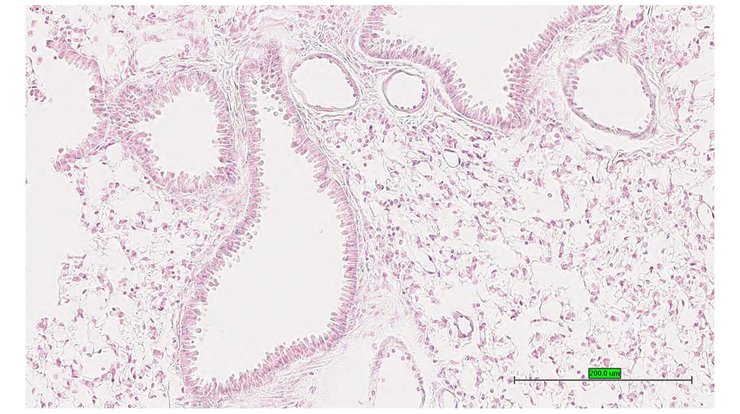

TS28: epididymis Present UC Davis_1886786

Specimen UC Davis_1886787: postnatal adult; Ncoa5tm1.1(KOMP)Mbp/Ncoa5+ (more )

Structure Level Pattern Image Note

TS28: epididymis Present UC Davis_1886787

Specimen UC Davis_1886788: postnatal adult; Ncoa5tm1.1(KOMP)Mbp/Ncoa5+ (more )

TS28: epididymis Present UC Davis_1886788